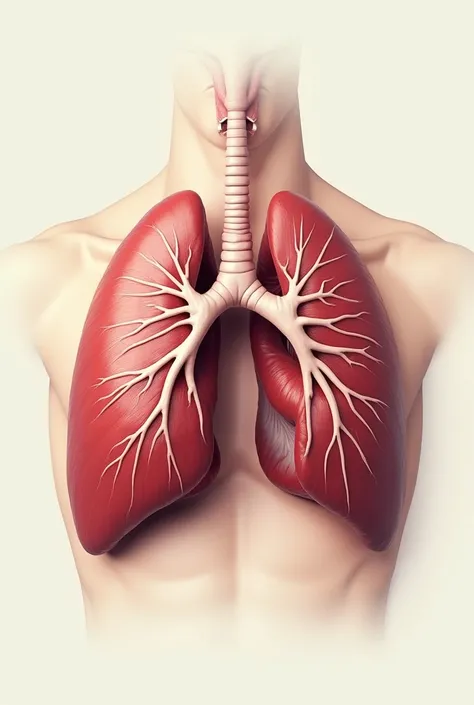

Make a folder about bacterial pneumonia

Make a folder about bacterial pneumonia